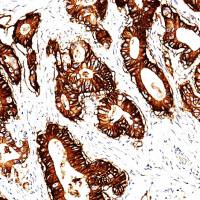

应用:此抗体可以与免疫球蛋白IgA的α链反应。免疫球蛋白A(IgA)在粘膜免疫中起关键作用。它存在于粘膜分泌物如泪液、唾液、初乳、肠液、阴道液、前列腺和呼吸道上皮细胞的分泌物中,并构成了粘膜表面的第一道防线。用于多发性骨髓瘤、淋巴瘤、浆细胞瘤、B细胞来源的霍奇金淋巴瘤和肾小球肾炎的研究。

阳性部位:细胞质

阳性对照:扁桃体